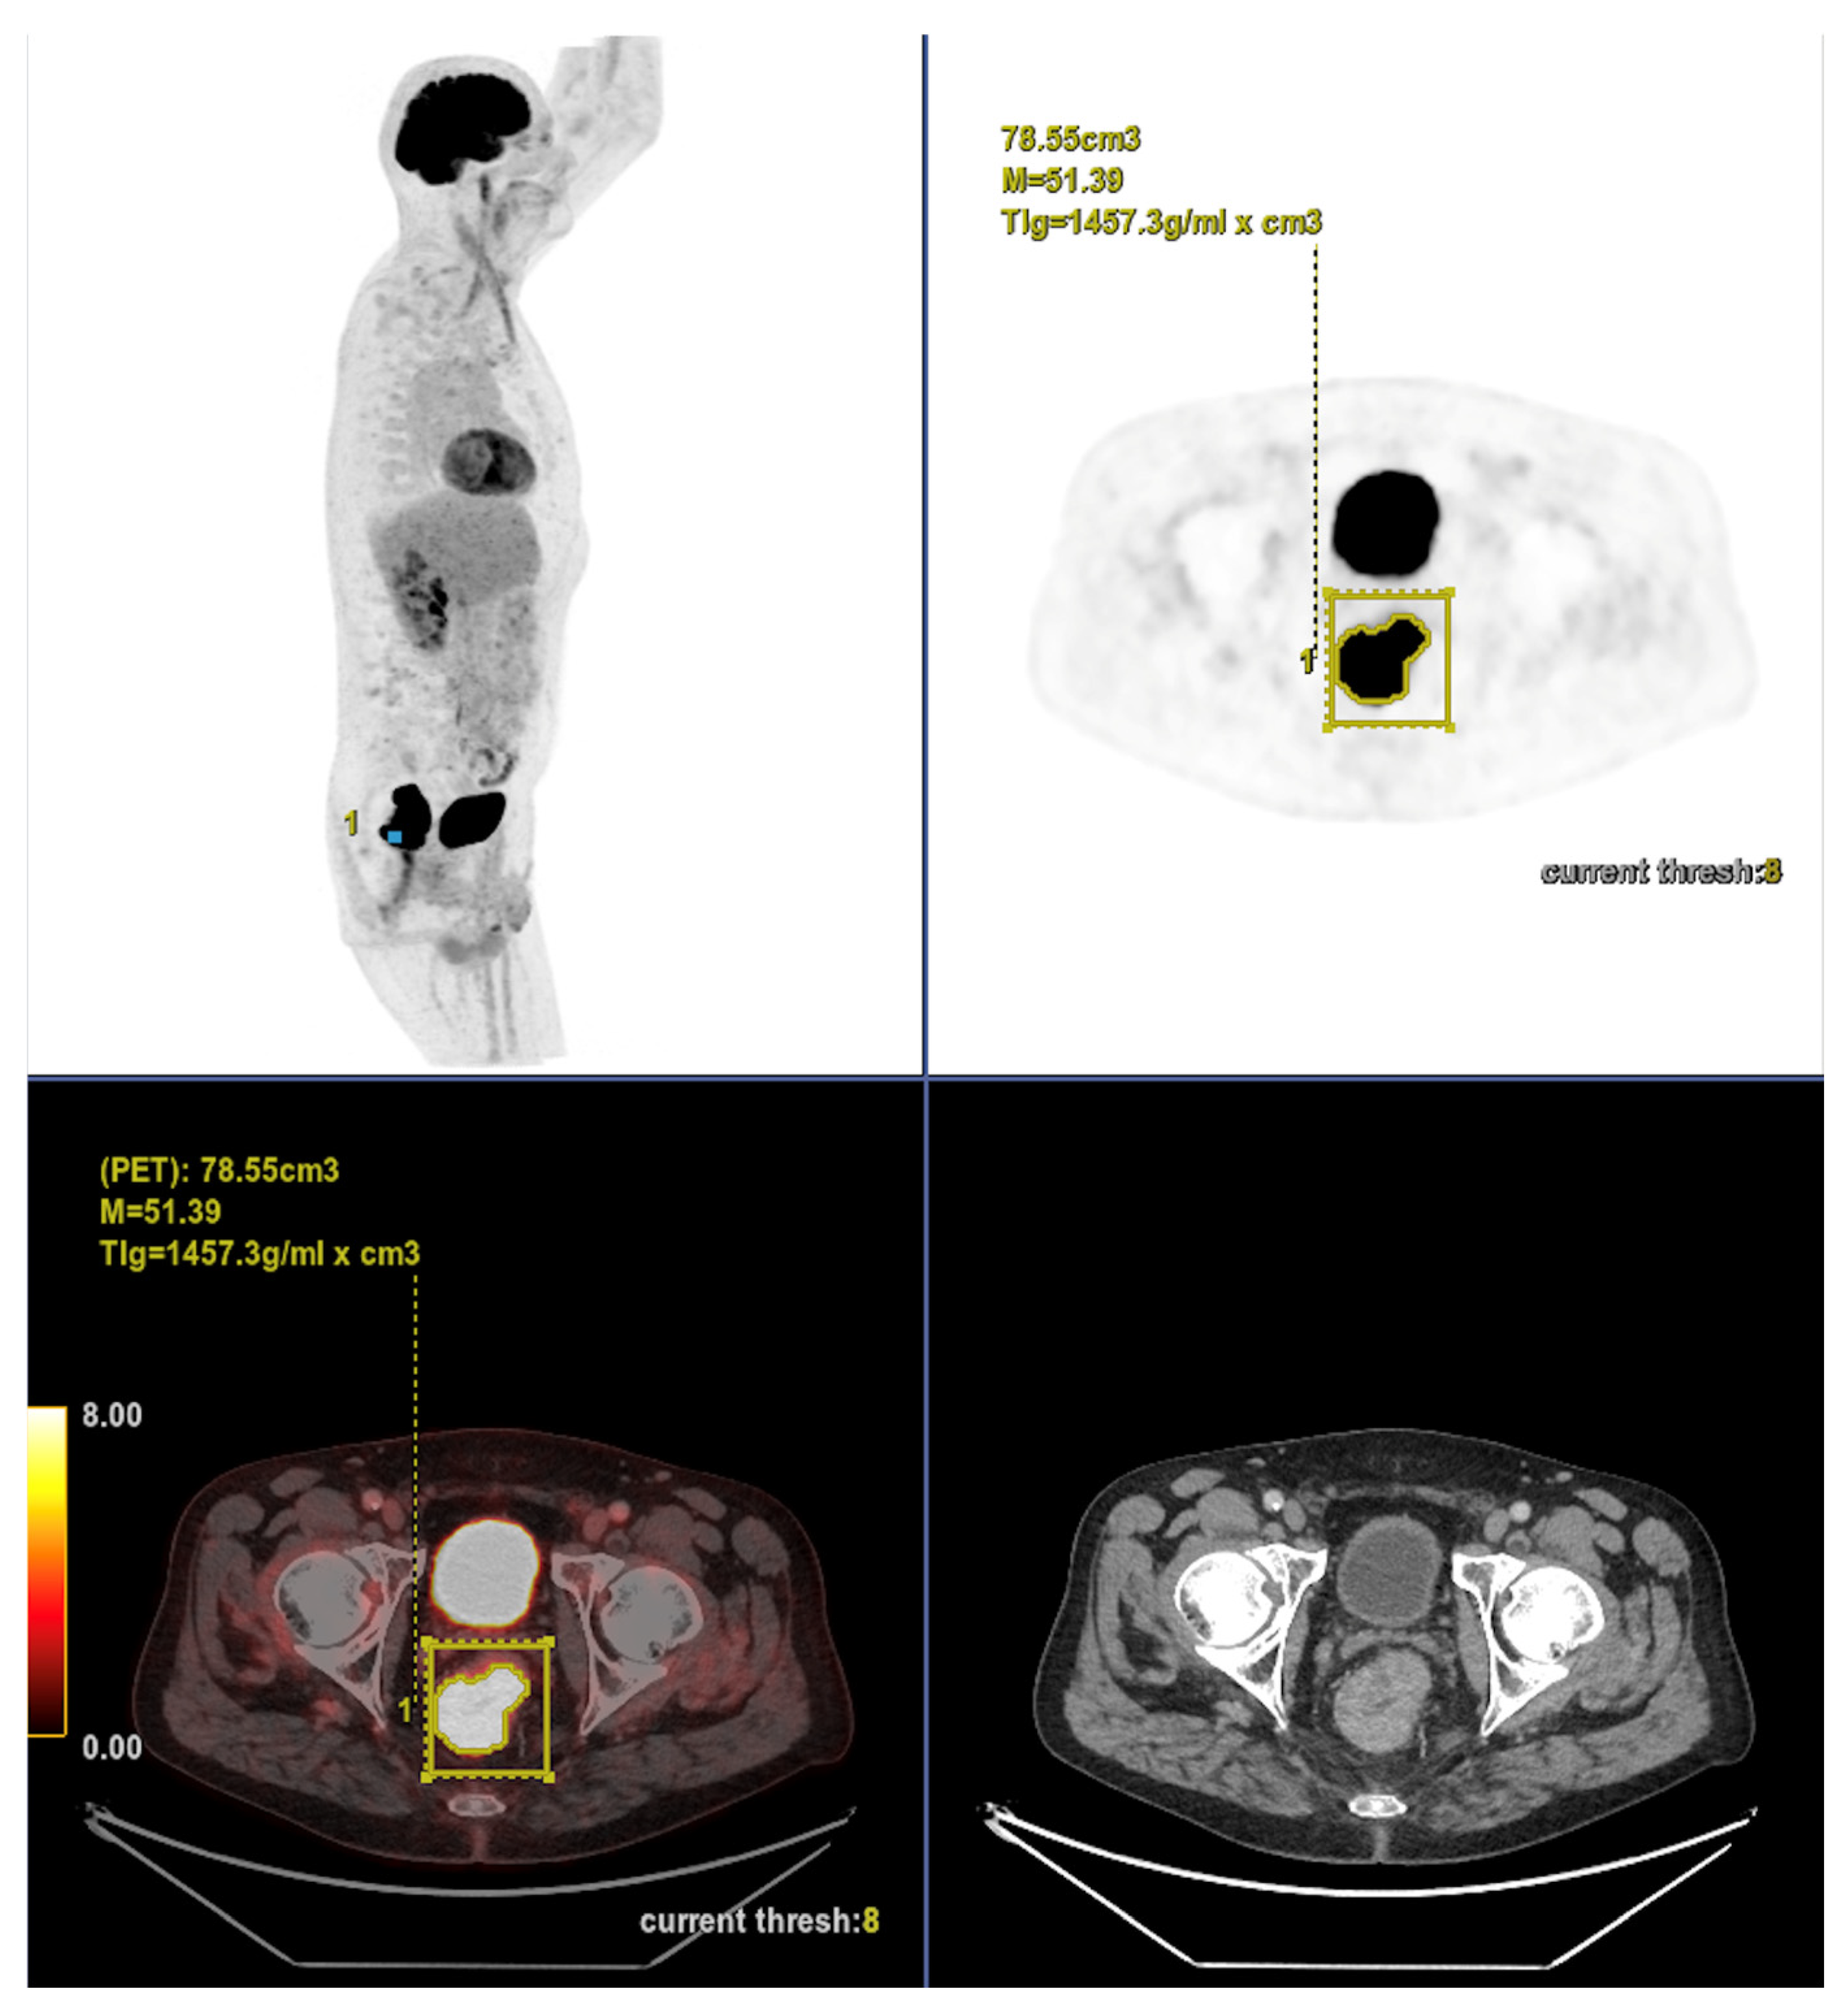

Altogether, these analyses demonstrate that MTV of the primary tumor is a consistent predictor of both OS and PFS. While OS was primarily influenced by sex and MTV, PFS was more strongly determined by UICC stage and MTV, as displayed in Figure 6. For a clearer understanding of the presented results, Figure 7 shows a representative example of manual delineation of the primary tumor on baseline FDG PET/CT.

Case 1: An 80-year-old patient with stage IVA rectal cancer and synchronous anal carcinoma, presenting with a large circumferential primary tumor showing a craniocaudal extension well above the predictive cut-off (13.0 cm vs. 6.2 cm; volume: 79.2 mL) and a metabolic tumor volume markedly exceeding both prognostic thresholds (MTV 79.0 vs. 35.49 for OS and 32.08 for PFS). Baseline FDG PET/CT demonstrates locoregional nodal involvement and a solitary liver metastasis in segment VII. The patient experienced rapid disease progression, with a progression-free survival of 8 months and an overall survival of 27 months.

Figure 7. Representative example of manual delineation of a primary rectal tumor on baseline FDG PET/CT showing manual delineation of the metabolically active tumor volume (first row) on the PET image with corresponding fused PET/CT image and CT image with iodinated contrast medium (second row). Morphological features, including tumor shape (circular or semi-circular), cranio-caudal extension (in cm), and overall tumor volume (in cm3), were assessed on the CT image (often with contrast medium) coregistered with the PET images. Tumor shape was determined on the axial plane, cranio-caudal extension on the sagittal plane, and tumor volume after careful delineation on all planes. Iodinated contrast medium was administrated in 70% of cases after exclusion of contraindications. Metabolic parameters, including SUVmax, SUVmean, MTV and TLG, were systematically extracted from the segmented tumor (yellow in this figure). SUVmax (M in this figure) and TLG were automatically displayed. SUVmean could be obtained by simply replacing SUVmax with SUVmean in the parameter selection. MTV was automatically calculated from TLG and SUVmean values displayed on the workstation. The highlighted region in yellow represents the 3D contour of the primary tumor, excluding physiological uptake and non-tumor regions.